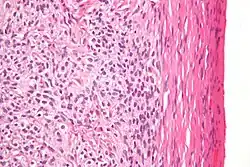

Definitive diagnosis of these tumours is based on the histology of tissue obtained in a biopsy or surgical resection. In a retrospective study of 72 cases in children and adolescents, the histology was important to prognosis.[8]